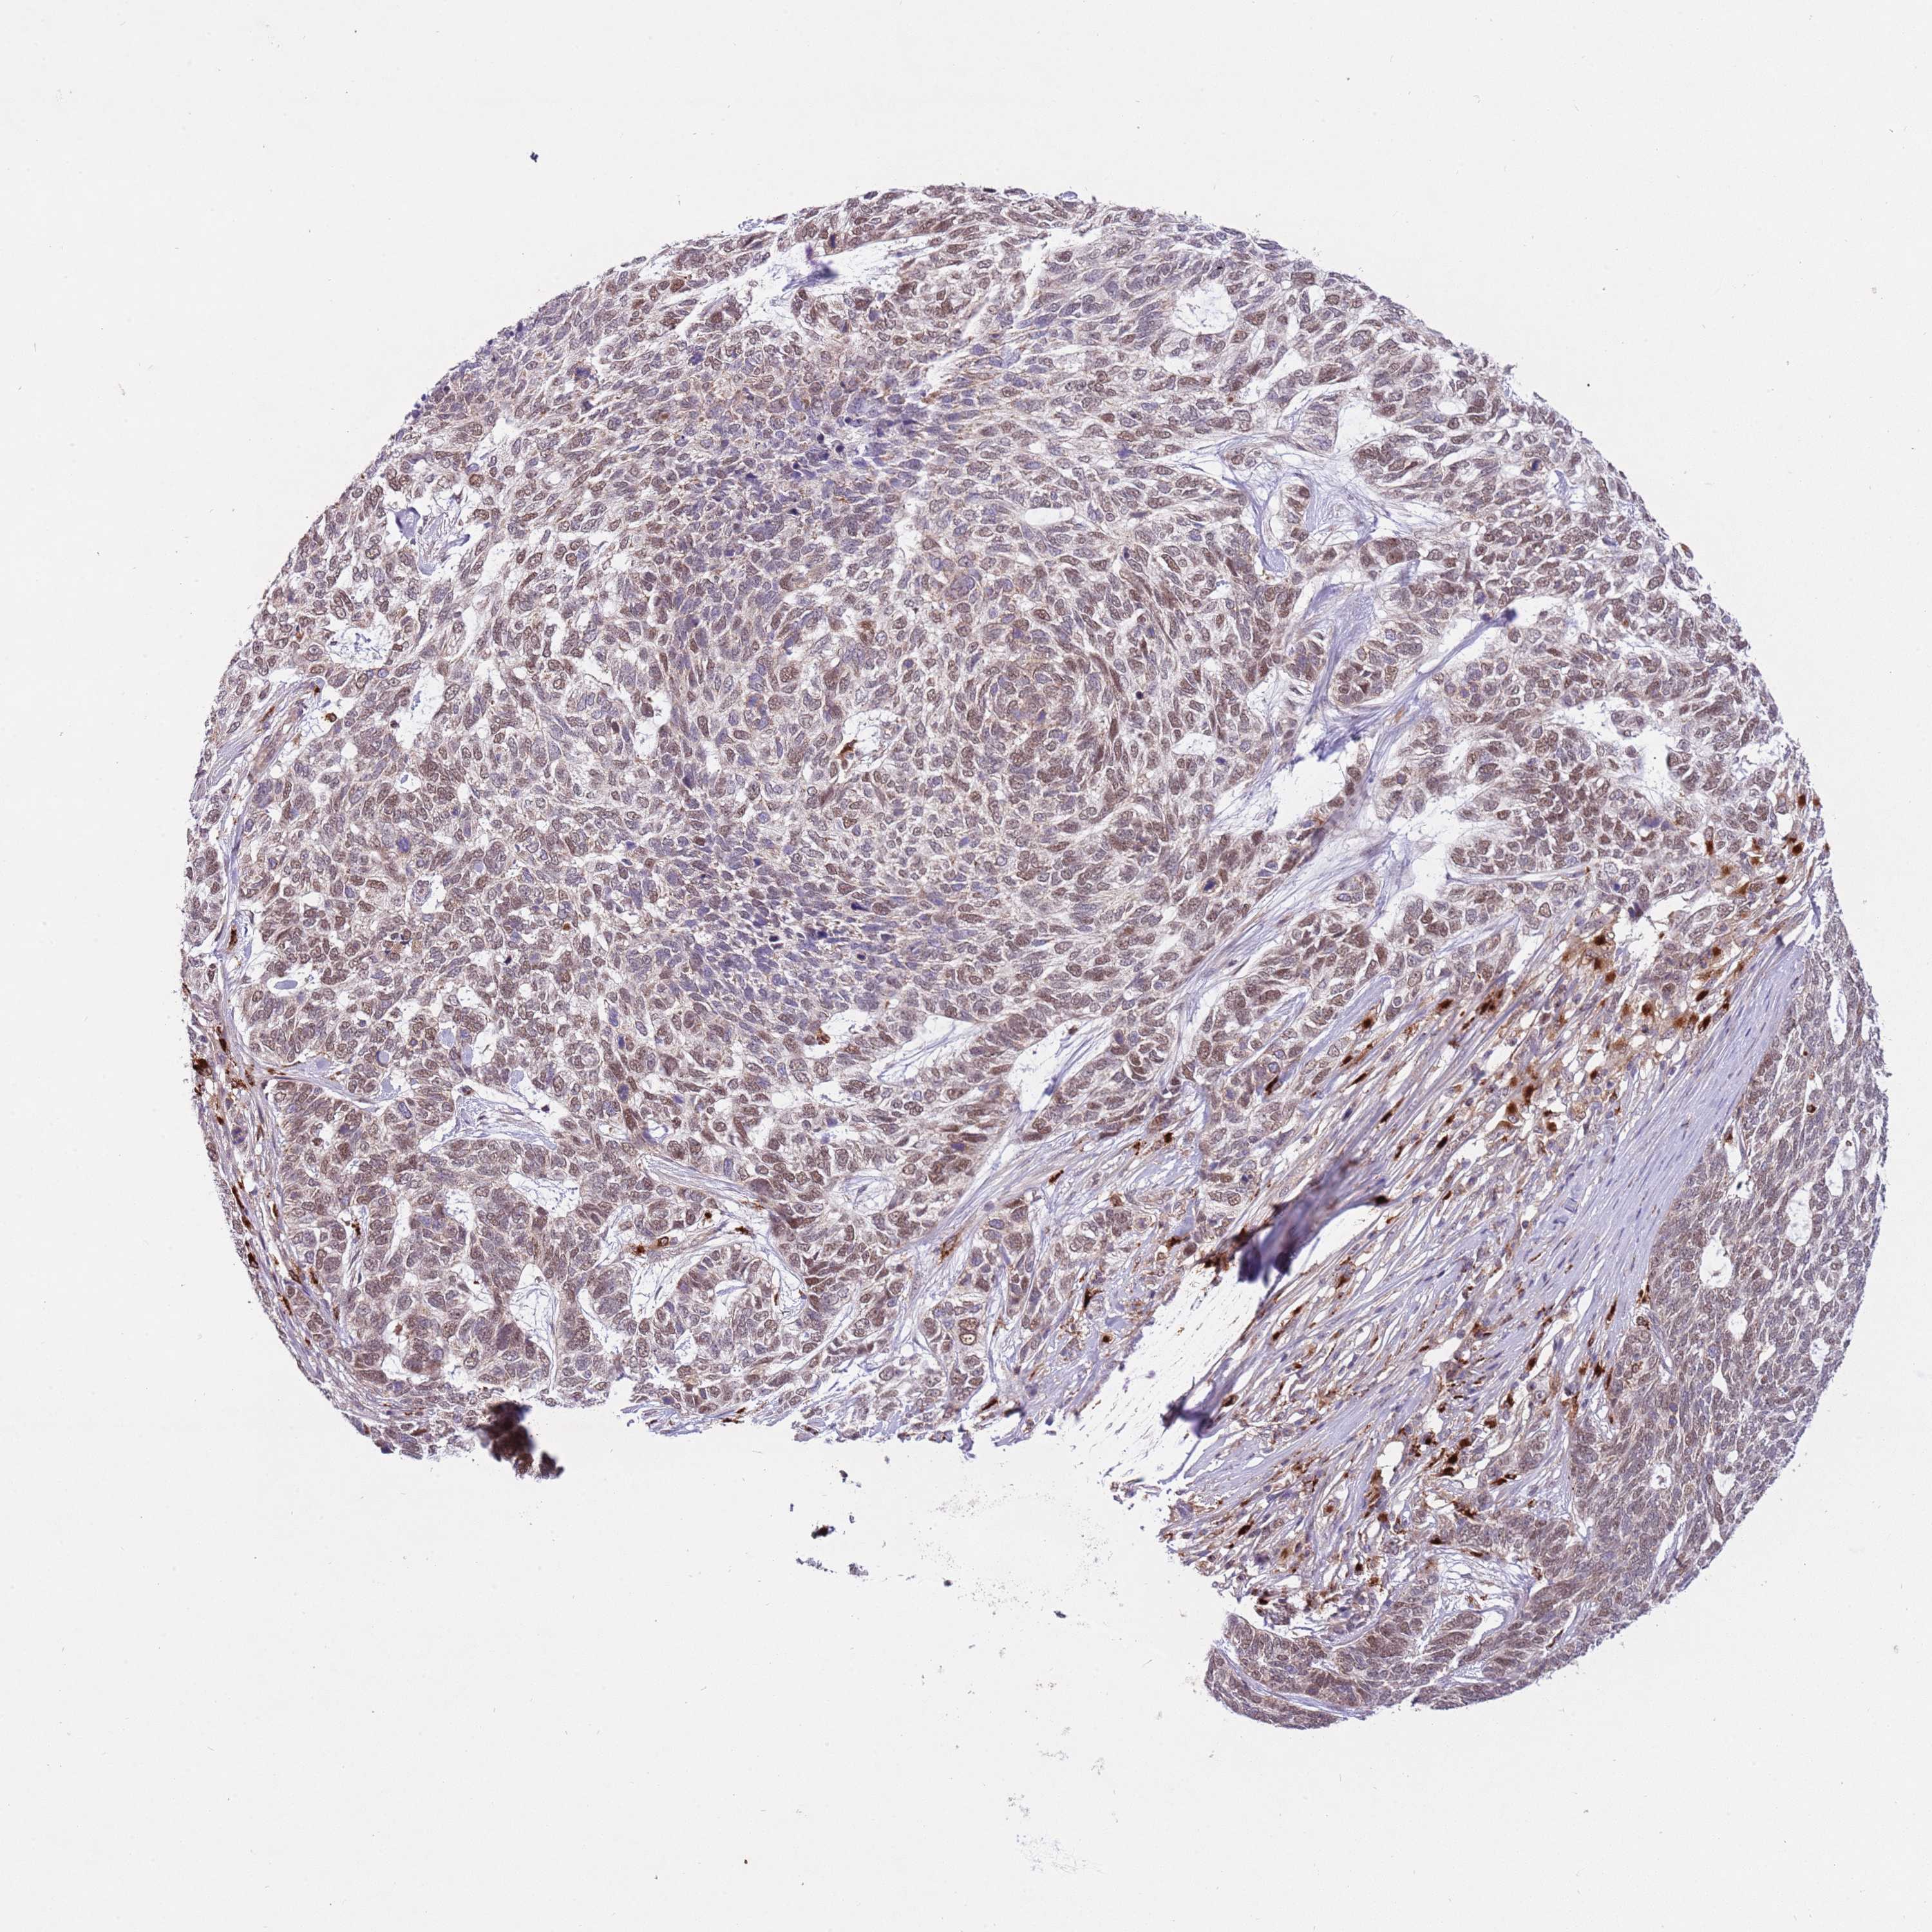

CANCER SKIN CANCER Show tissue menu

Basal cell and squamous cell cancer

SKIN CANCER - Protein expressioni

A mouse-over function shows sample information and annotation data. Click on an image to view it in a full screen mode. Samples can be filtered based on level of antibody staining by selecting one or several of the following categories: high, medium, low and not detected. The assay and annotation is described here.

Each image is clickable and will lead to virtual microscopy that enables deeper exploration of all samples and also displays staining intensity scores, fraction scores and subcellular localization as well as patient and tissue information for each sample.

Antibody HPA048684

Staining

High

Strong

Quantity

Location

Basal cell carcinoma

Squamous cell carcinoma, NOS

Squamous cell carcinoma, metastatic, NOS

Squamous cell carcinoma in situ, NOS